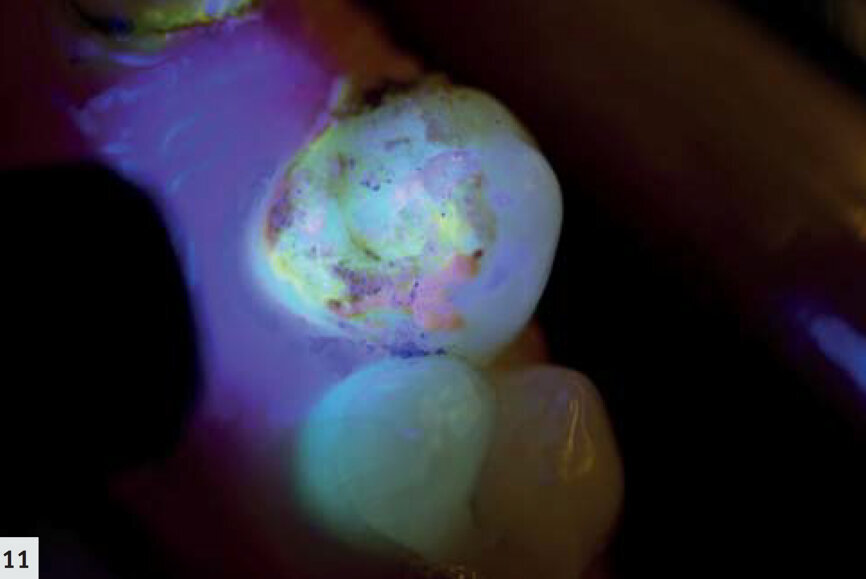

Figs. 11–12 : Bridge adhésif détaché. La fluorescence rouge émise par les porphyrines, les produits métaboliques des bactéries buccales, démontre la présence d’un biofilm mature.

Une fluorescence rouge du biofilm est généralement attribuée à la présence d’un biofilm mature et elle trouve son origine dans les porphyrines, indiquant une activité métabolique.5 Les figures 11 et 12 présentent un bridge adhésif détaché. Sur la figure 13, on peut observer le biofilm adjacent au rebord gingival.

Une fluorescence rose orangée peut être observée, principalement au niveau des surfaces plus rugueuses, ce qui indique clairement les sites d’accumulation de la plaque. Ces sites sont liés au risque carieux et à l’inflammation parodontale, et ils peuvent être détectés en un coup d’oeil grâce à ces caractéristiques.